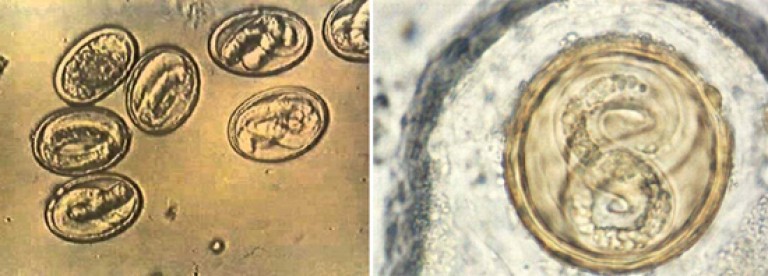

Микрофотографии яиц гельминтов Toxocara canis

Раздел: Фотоэссе